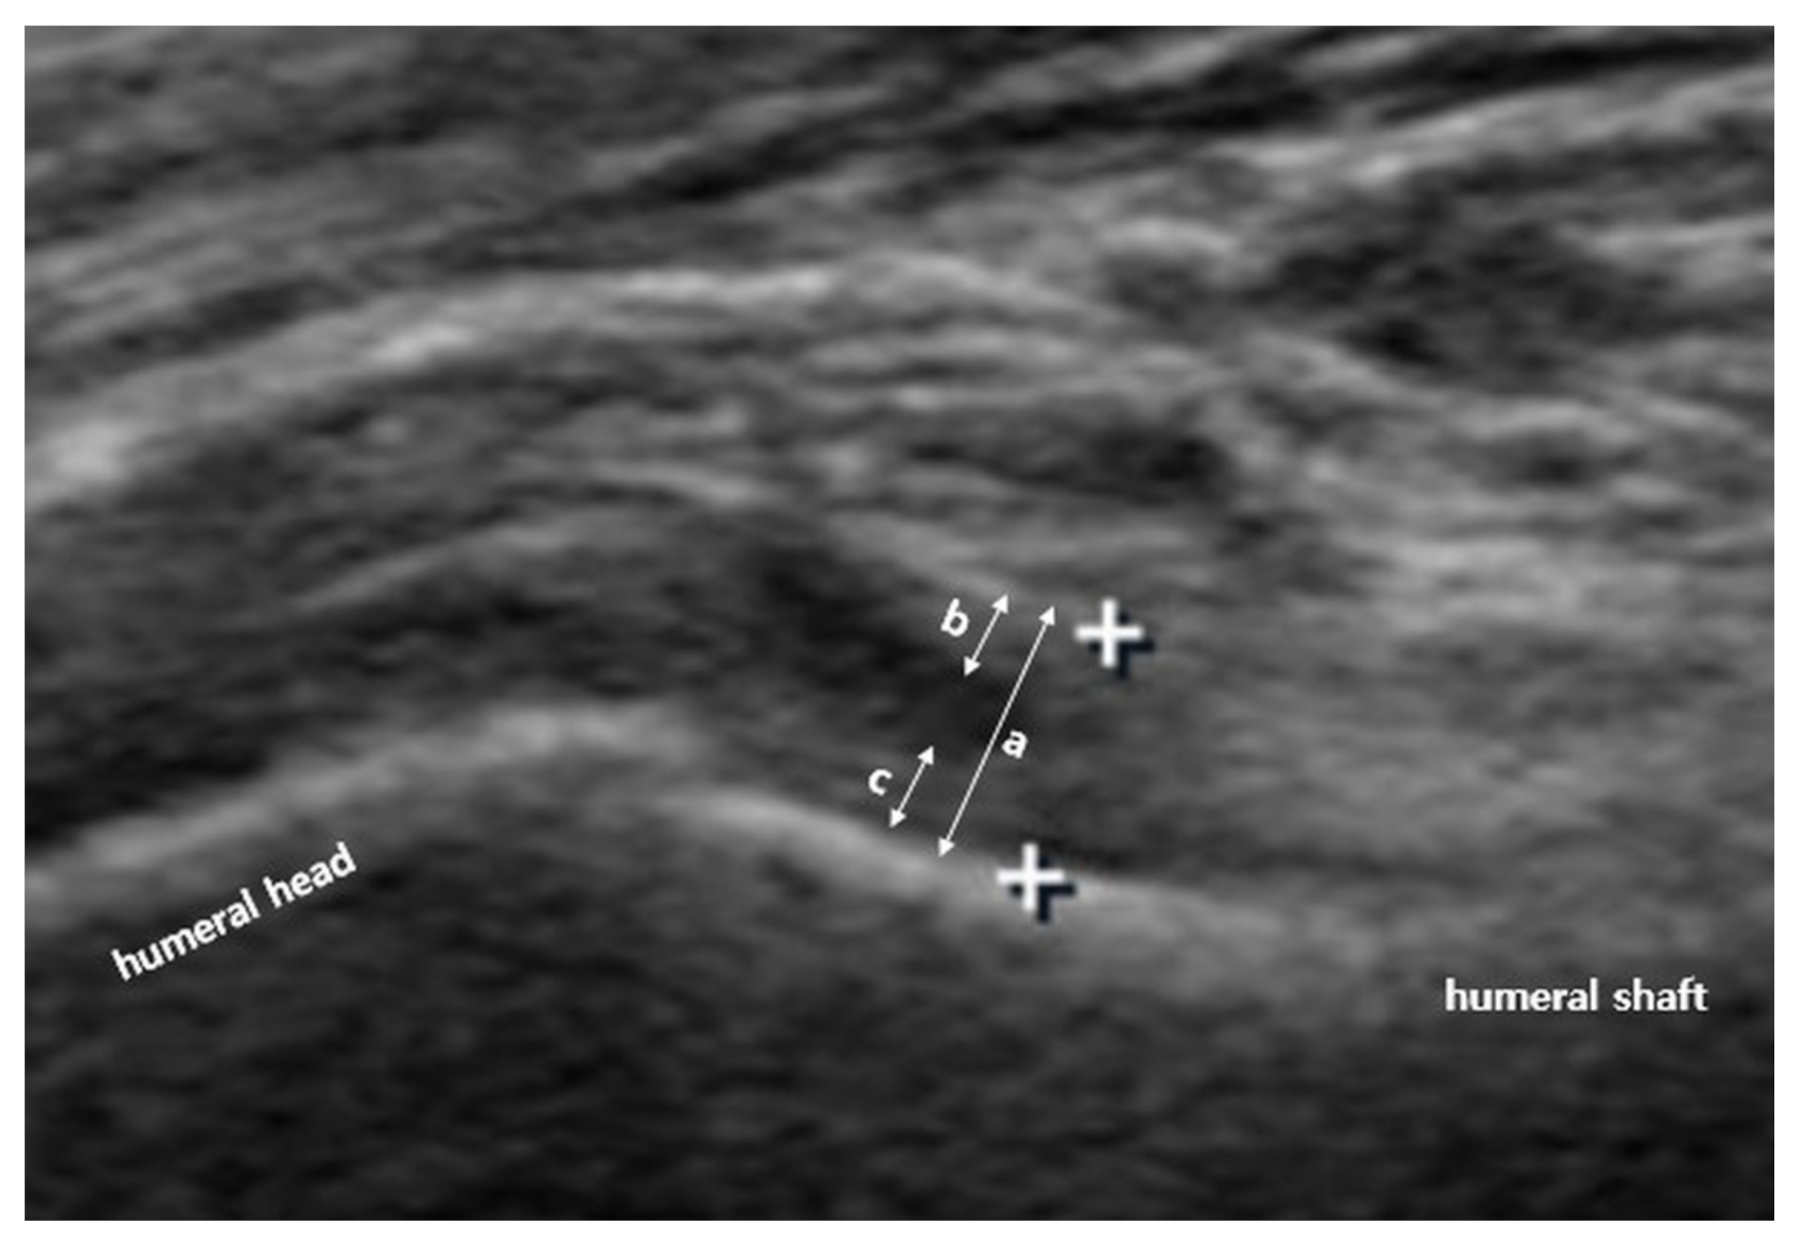

Figure 2.

Ultrasonographic measurement of inferior joint capsule (IJC) thickness. IJC thickness was defined as the distance from the cortex of the humerus to the outer margin of the capsule at the widest portion of the capsule. IJC thickness (a) includes both the glenoid side (b) and humeral side (c).

US investigation of the IJC was performed by a single physiatrist with more than 15 years of experience in musculoskeletal US. A linear 5–12-MHz probe (HD15 ultrasound system; Philips, Amsterdam, The Netherlands) was used. Based on a previously reported protocol, to measure the IJC thickness in the neutral position, the patient was laid in a supine position with the shoulder abducted 40° and elbow flexed 90°; the transducer was placed around the anterior axillary line to visualize the cortex of the humerus (Figure 1). To measure the IJC thickness in the externally rotated and internally rotated position, the patients maximally rotated their upper arm with their palms facing the sky or ground, respectively, with the shoulder abducted 40° (Figure 1). A still image that best showed the IJC near the anatomic neck of the humerus was selected and saved, and the IJC thickness was measured using the caliper of the ultrasound machine. IJC thickness was defined as the distance from the cortex of the humerus to the outer margin of the capsule at the widest portion of the capsule (Figure 2). Thus, the IJC thickness includes both the humeral and glenoid sides that make up the entire IJC (Figure 2). These parameters were measured on both the affected and unaffected sides.